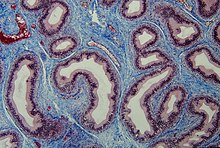

Le tissu conjonctif (TC) est l'un des quatre types de tissus biologiques du règne animal qui soutient, lie, ou distingue différents types de tissus et d'organes du corps. Il tient son origine dans le mésoderme, au moment de la gastrulation, lors du développement embryonnaire. Les trois autres types de tissus sont l'épithélium, le tissu musculaire et le tissu nerveux. Le tissu conjonctif se place entre d'autres tissus du corps, comme ceux du système nerveux. Le tissu conjonctif compose notamment les membranes externes qui enveloppent l'encéphale et la moelle spinale, ces deux constituant le système nerveux central, touchant la substance grise et la substance noire, la plus profonde. Il compose aussi les os, les vaisseaux sanguins et le sang, tous les organes comme les yeux, la peau, etc. et constitue 80 % du corps humain. Grande découverte de la fin du XXe siècle, 200 maladies orphelines du tissu conjonctif sont aujourd'hui recensées.

Mis à part le sang et la lymphe, les tissus conjonctifs possèdent trois principaux constituants : les fibres (élastiques et collagéneuses)[1], la substance fondamentale et la cellule — toutes les autorités scientifiques n'évaluent pas le sang ou la lymphe en tant que tissu conjonctif[2]. Ils s'immergent dans un liquide corporel aqueux.